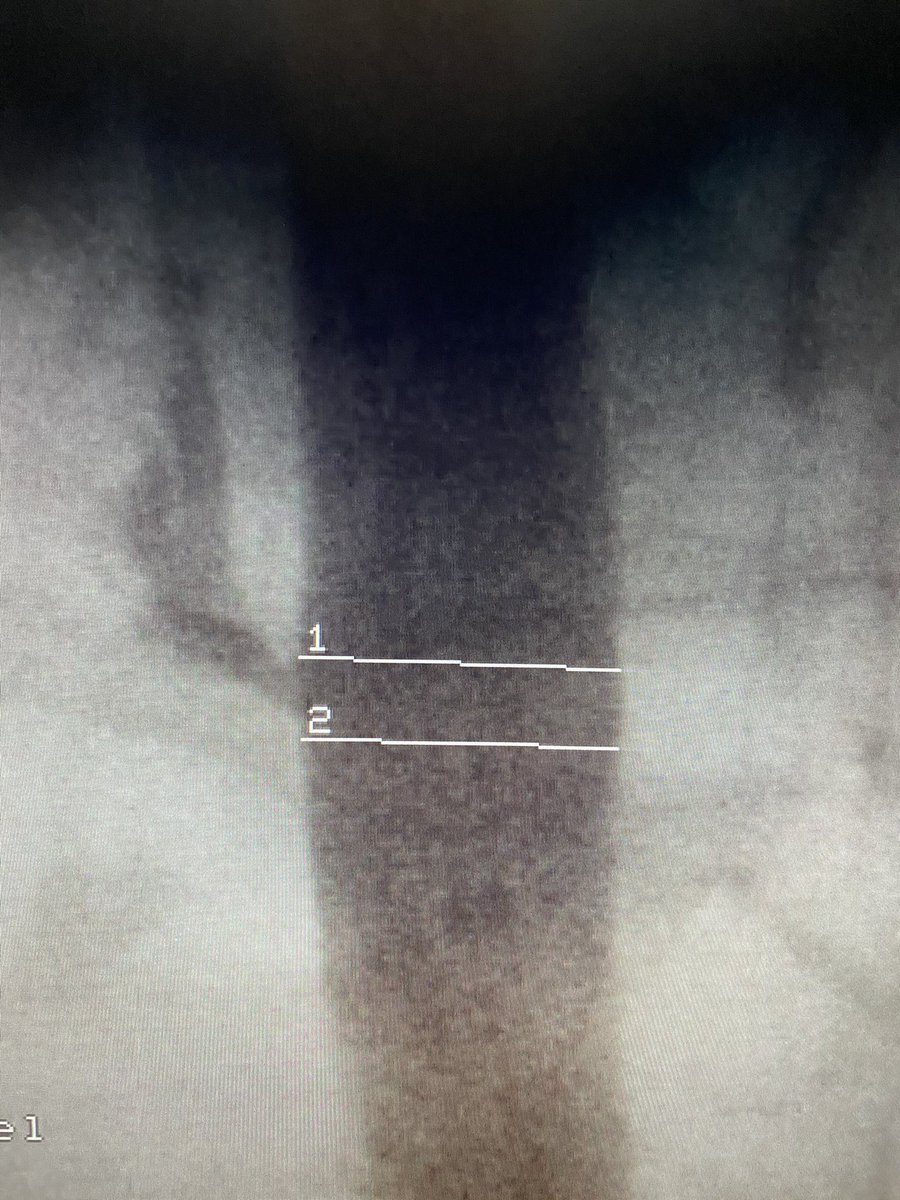

@PamelaMasonEP That is one of the reason I switched to stick the vein before cutting down to form the pocket. (Or do a venogram). Impressive lead positioning, but would have been easier from the right.